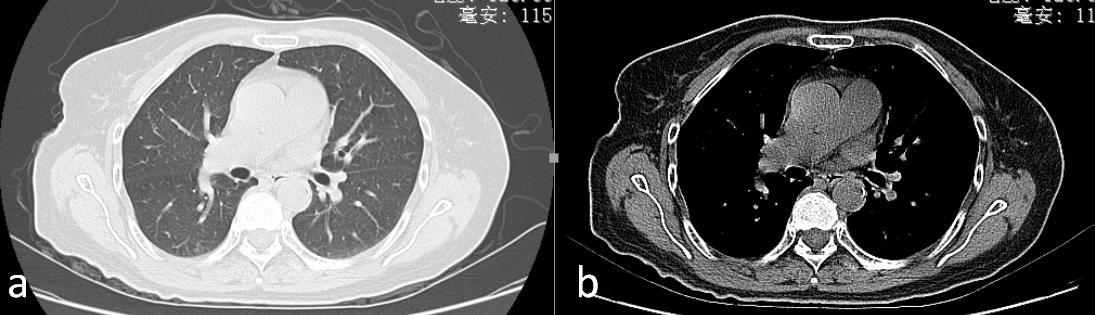

CT诊断与病理检查的优缺点

如果将CT与病理检查来比较,应该是各有所长,并不能互相替代。

CT的强项在于能够敏感地看到肺部是不是有问题,问题在哪里,大致是什么性质的问题,漏诊比较少。但在具体病灶性质的细节方面还有缺陷,最权威的专家也不敢说绝对不会出现误诊。

而病理检查的强项就在于通过所取得的病理标本,能够准确地判断病灶的病理性质,假如是肿瘤,它不但能够明确是肿瘤,还能准确地判断是什么类型,是小细胞肺癌还是非小细胞肺癌,是腺癌、鳞癌、还是腺鳞癌,分辨出神经内分泌癌、多形性癌、梭形细胞癌、巨细胞癌、癌肉瘤及肺母细胞瘤等少见的恶性肿瘤类型,甚至能够做到更为精确的基因分型。但病理检查的缺陷在于可能取不到肿瘤标本,或者看不到病理组织,漏诊的风险比较大。